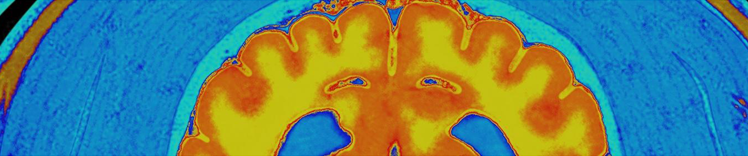

神经元质量和脑 MRI

- 某些部位组织萎缩(缩减)

- 脑室体积增大

成年宠物的大脑依靠葡萄糖来获取能量。随着年龄的增长,即使存在葡萄糖,大脑利用葡萄糖作为能量来源的能力也会有所降低。由于大脑需要的能量较高,所以在能量代谢改变导致能量供应不足时特别容易受到影响。大脑中葡萄糖代谢减少会引发连锁反应,最终可能导致脑细胞死亡和不可逆转的脑质量下降以及体格和行为的改变。